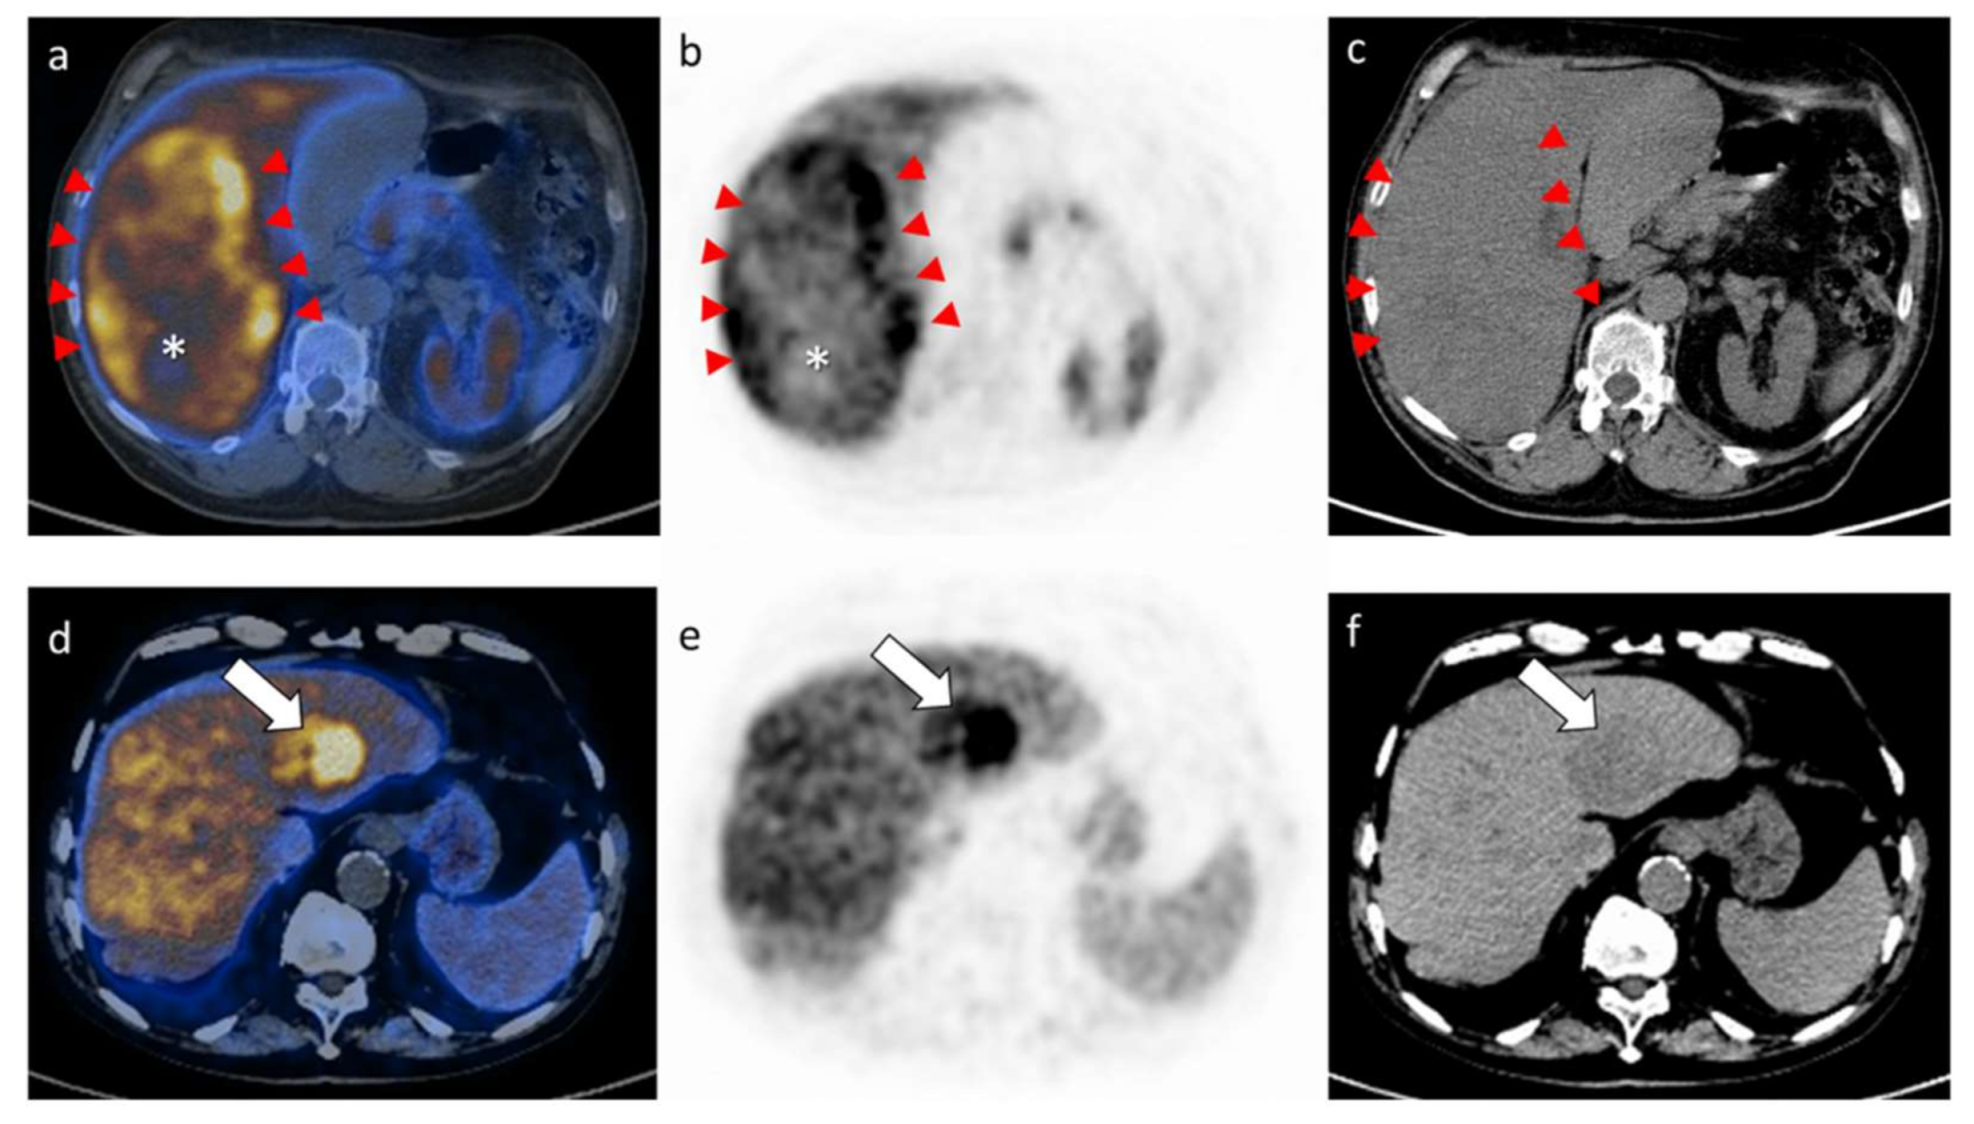

2.2. Results of the PET/CT Parameters

4.6. 11C-choline PET/CT